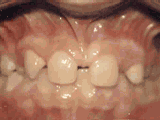

牙列稀疏,牙槽骨過長,或者牙齒少,導(dǎo)致排列太寬松,零零散散,經(jīng)過矯正后的是這樣的~